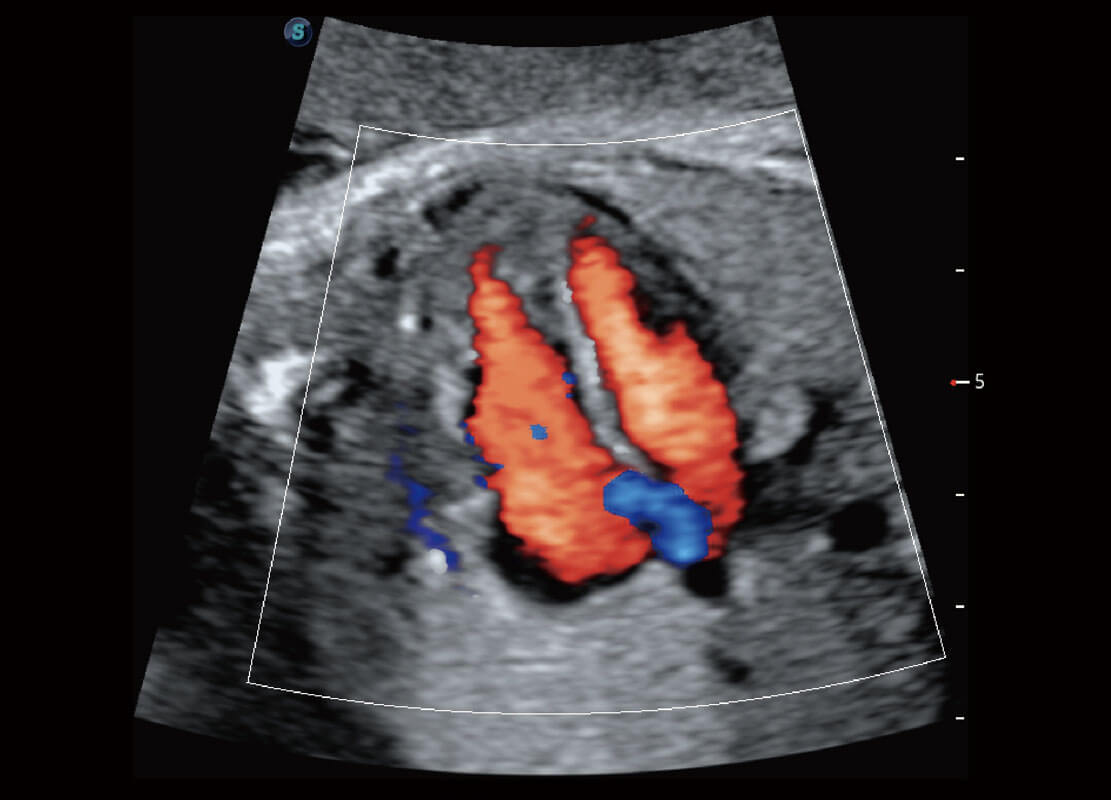

P60搭载一系列胎儿心脏成像技术,实现精细的胎儿心脏评估。

四腔心血流

右室双出口